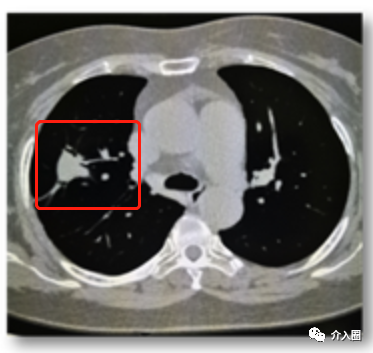

早期肺癌應用實例(來源:康博刀官方資料)

患者信息:臨床診斷早期肺癌,若行外科手術切除,切除范圍至少要超過病灶邊緣2cm,甚至需要進行肺葉切除。冷凍消融可以實現(xiàn)精準治療,減少對機體正常組織的損傷

治療方案及過程:采用冷凍消融

治療結果:冷凍消融消融范圍范圍僅超過病灶邊緣1cm,對肺功能的損傷較小

▲圖10 治療過程